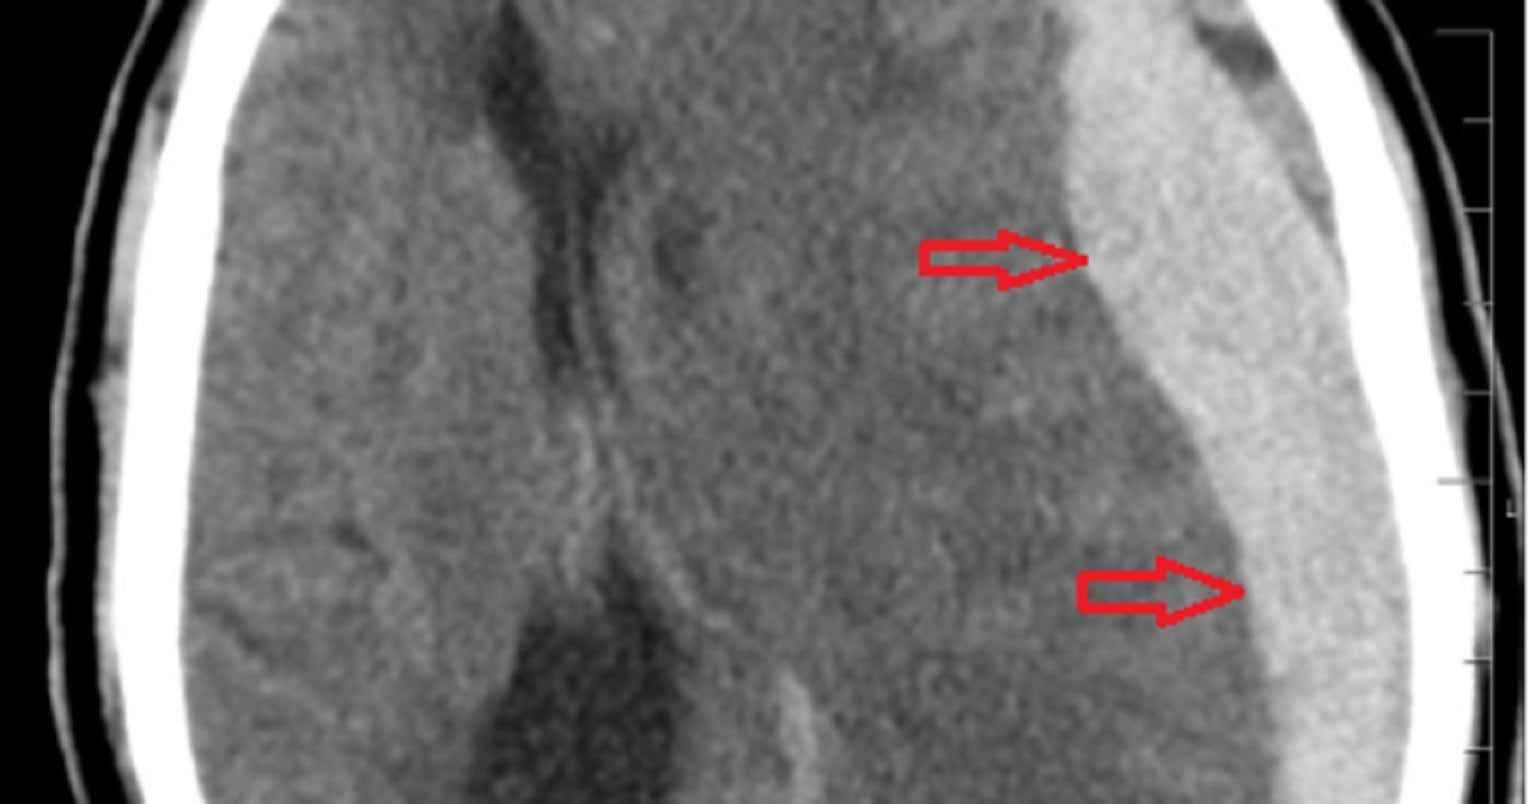

El mangaka Akira Toriyama falleció a los 68 años a causa de un hematoma subdural. Se trata de una acumulación de sangre entre las capas de tejido que recubren el cerebro.

El cerebro está protegido por tres capas de tejido llamadas meninges: la duramadre (la capa más externa y resistente), la aracnoides (una capa delgada en medio) y la piamadre (la capa más interna, que está en contacto directo con el cerebro). Entre la duramadre y la aracnoides hay un espacio llamado espacio subdural, el cual normalmente contiene solo una pequeña cantidad de líquido cerebroespinal.

Cuando ocurre un trauma en la cabeza, como un golpe o una caída, los vasos sanguíneos que atraviesan el espacio subdural pueden romperse, causando una acumulación de sangre. Este sangrado puede comprimir el tejido cerebral y causar una serie de síntomas, que van desde leves hasta potencialmente mortales, dependiendo del tamaño y la ubicación del hematoma.

Los hematomas subdurales se clasifican generalmente en agudos, subagudos o crónicos según la rapidez con la que se desarrollan los síntomas y la aparición del sangrado. Los hematomas agudos suelen ser el resultado de un trauma reciente y pueden causar síntomas graves rápidamente. Los subagudos tienen una progresión de síntomas más lenta, y los crónicos pueden desarrollarse durante semanas o meses.